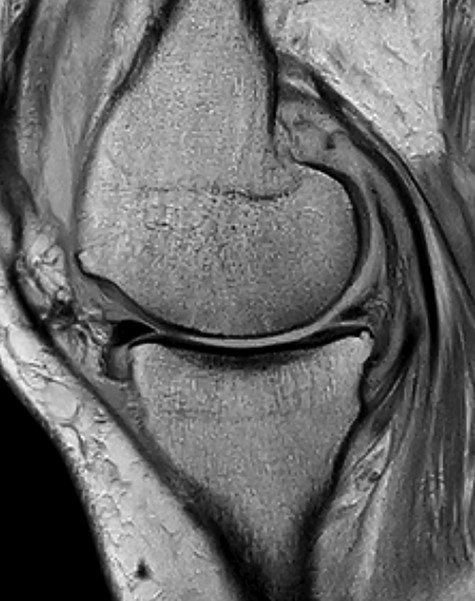

Conventional radiographs in an anteroposterior and lateral view showed advanced osteoarthritis (Kellgren stage III) accentuated medially and patellofemoral (Figs 1 and 2). An additional magnetic resonance imaging (MRI) was performed, which confirmed the medial accentuated osteoarthritis, it revealed some minor meniscal tears, some signs of general synovitis and joint effusion (Figs 3 and 4).